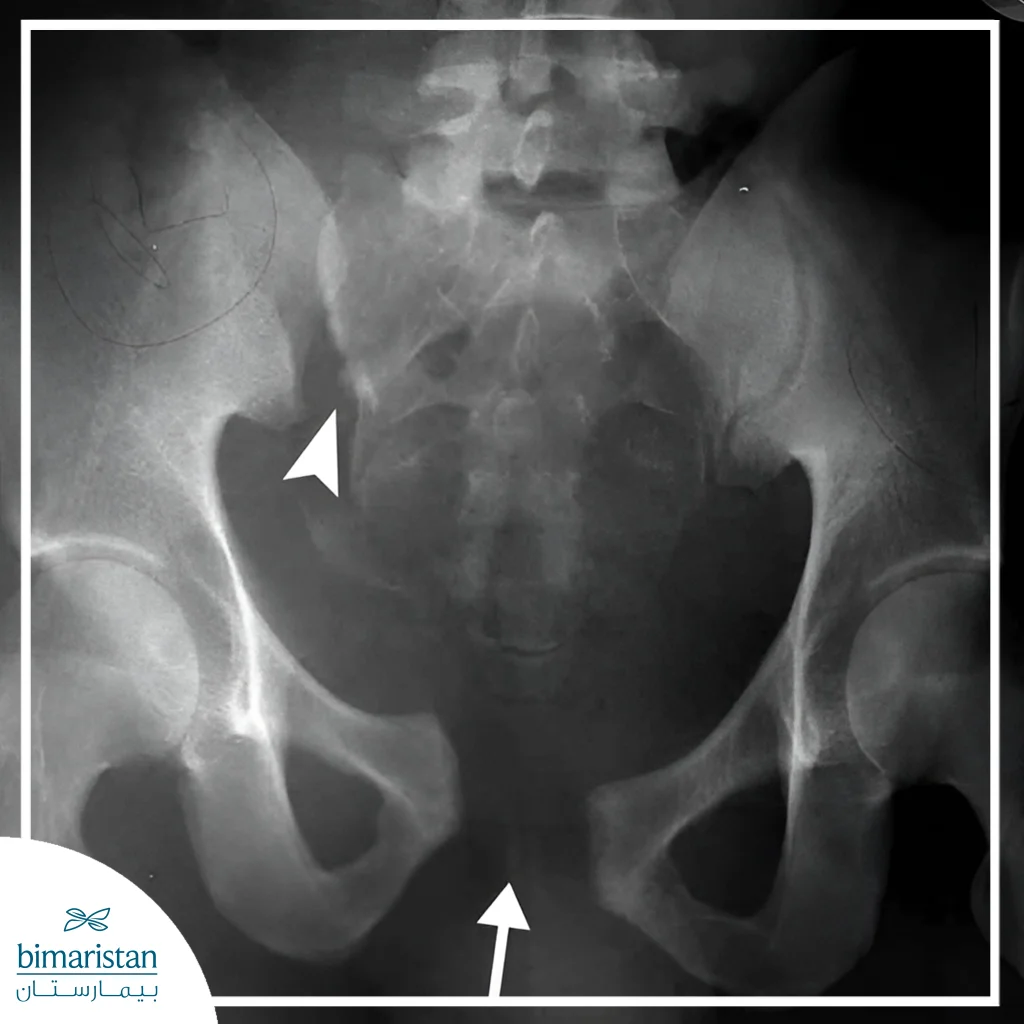

X-rays

X-rays are the first imaging technique used to confirm the presence of a fracture and determine its pattern, such as closed or open fractures and partial or complete fractures. Although effective, they may not always detect simple fractures or stress fractures, but they provide essential information for pelvic fracture treatment planning.

Computed tomography (CT) is an accurate tool for evaluating complex pelvic fractures, providing three-dimensional images of the bones, revealing small or displaced fractures that may not show up on X-rays. CT helps to accurately determine the stability of the pelvis and is essential before any surgical intervention in a pelvic fracture treatment plan.